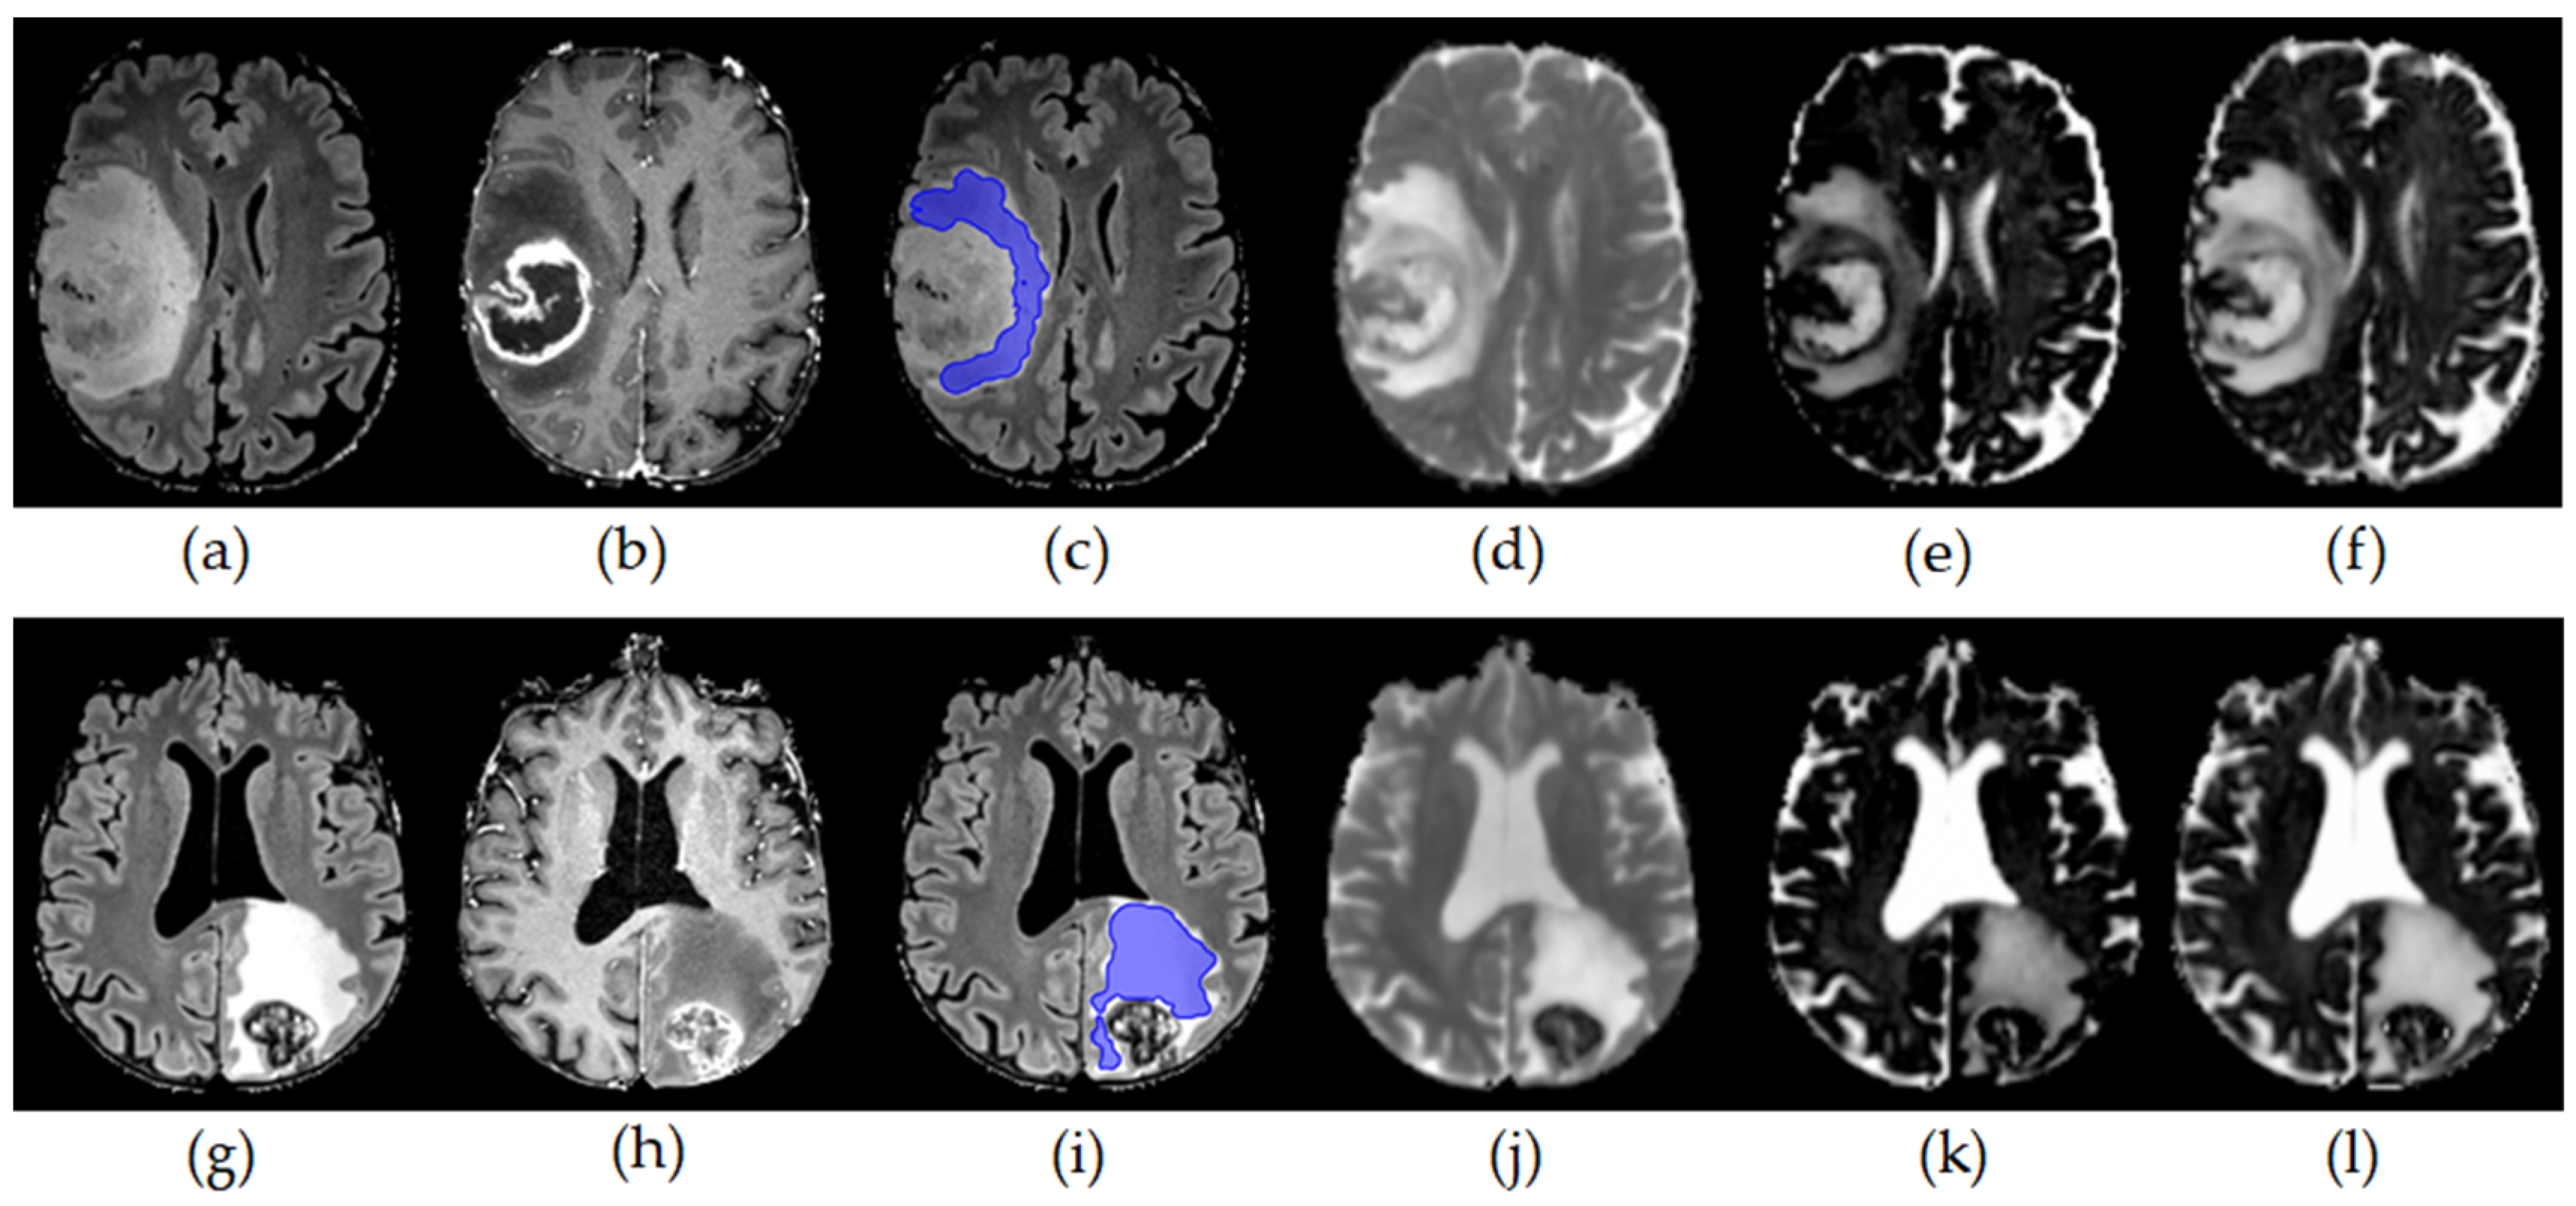

- Würtemberger, U.; Diebold, M.; Erny, D.; Hosp, J.A.; Schnell, O.; Reinacher, P.C.; Rau, A.; Kellner, E.; Reisert, M.; Urbach, H.; et al. Diffusion Microstructure Imaging to Analyze Perilesional T2 Signal Changes in Brain Metastases and Glioblastomas. Cancers 2022, 14, 1155. [Google Scholar] [CrossRef]